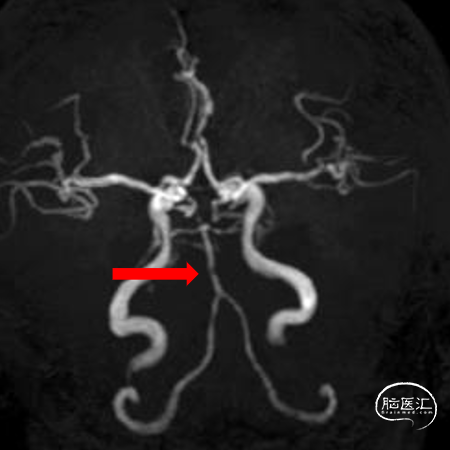

MRA:基底动脉重度狭窄

造影示:右侧优势椎,经右侧椎动脉导弯造影,双侧胚胎型大脑后动脉。

基底动脉狭窄位于双侧AICA开口处,且无双侧PICA,其供血区由双侧AICA、SCA分支代偿供血。

术后造影:基底动脉狭窄消失,双侧AICA通畅。